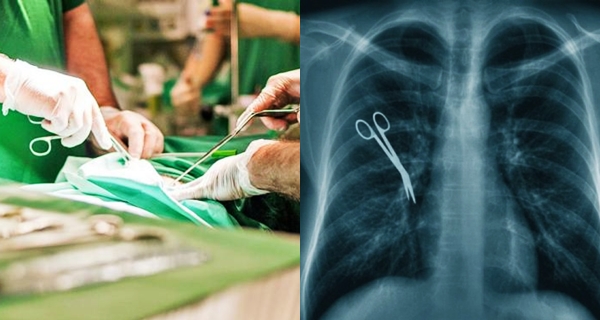

7 Kasus malapraktik mengerikan yang terjadi dalam dunia medis